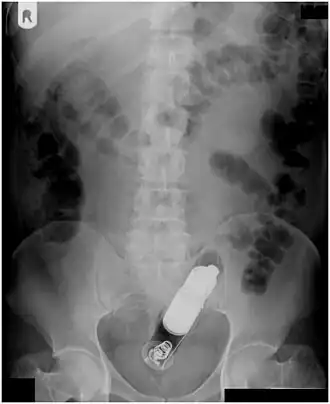

| Radiografia de abdômen masculino com vibrador no reto | |

Normalmente, várias imagens radiológicas são registradas para localizar com precisão o lugar e a profundidade do corpo estranho. Isso geralmente é feito por raio-X. Corpos estranhos feitos de material de baixo contraste (por ex. plástico) podem exigir ultrassom médico ou uma tomografia computadorizada.[29] ressonância magnética é contraindicada, especialmente se o corpo estranho for desconhecido. Corpos estranhos retais podem penetrar profundamente no cólon, em certas circunstâncias até a flexura cólica direita.[11]